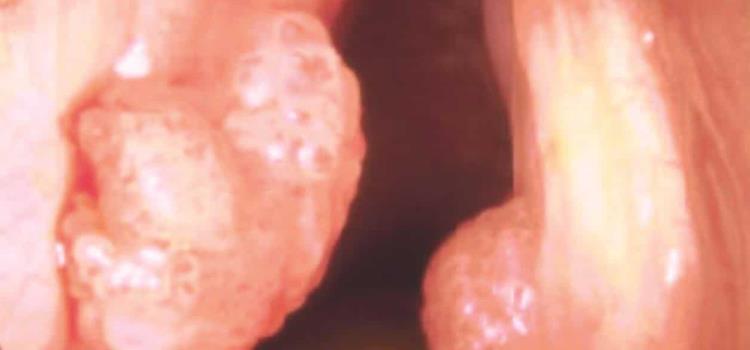

El Virus del Papiloma Humano (VPH) es causante del 99:9 % de todos los cánceres del cuello uterino, es una pandemia que trata de contenerse con la vacuna; también está relacionado con cáncer de pene, vulva, vaginal, orofaríngeo, anal y cervical, así como verrugas genitales.

El oncólogo del Hospital de la Ciudad de México, Roberto Moziños Montes, hizo saber por medio de una tabla que en ésta se puede apreciar que las verrugas genitales representan más de 30 millones de casos por año en ambos sexos, y que éstas están asociadas al VPH.